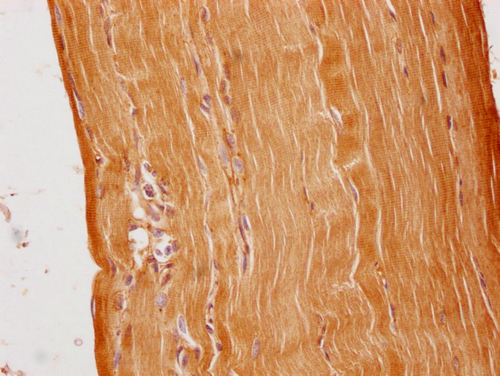

• IHC image of CSB-PA003654PA01HU diluted at 1:100 and staining in paraffin-embedded human skeletal muscle tissue performed on a Leica BondTM system. After dewaxing and hydration, antigen retrieval was mediated by high pressure in a citrate buffer (pH 6.0). Section was blocked with 10% normal goat serum 30min at RT. Then primary antibody (1% BSA) was incubated at 4°C overnight. The primary is detected by a Goat anti-rabbit polymer IgG labeled by HRP and visualized using 0.05% DAB.